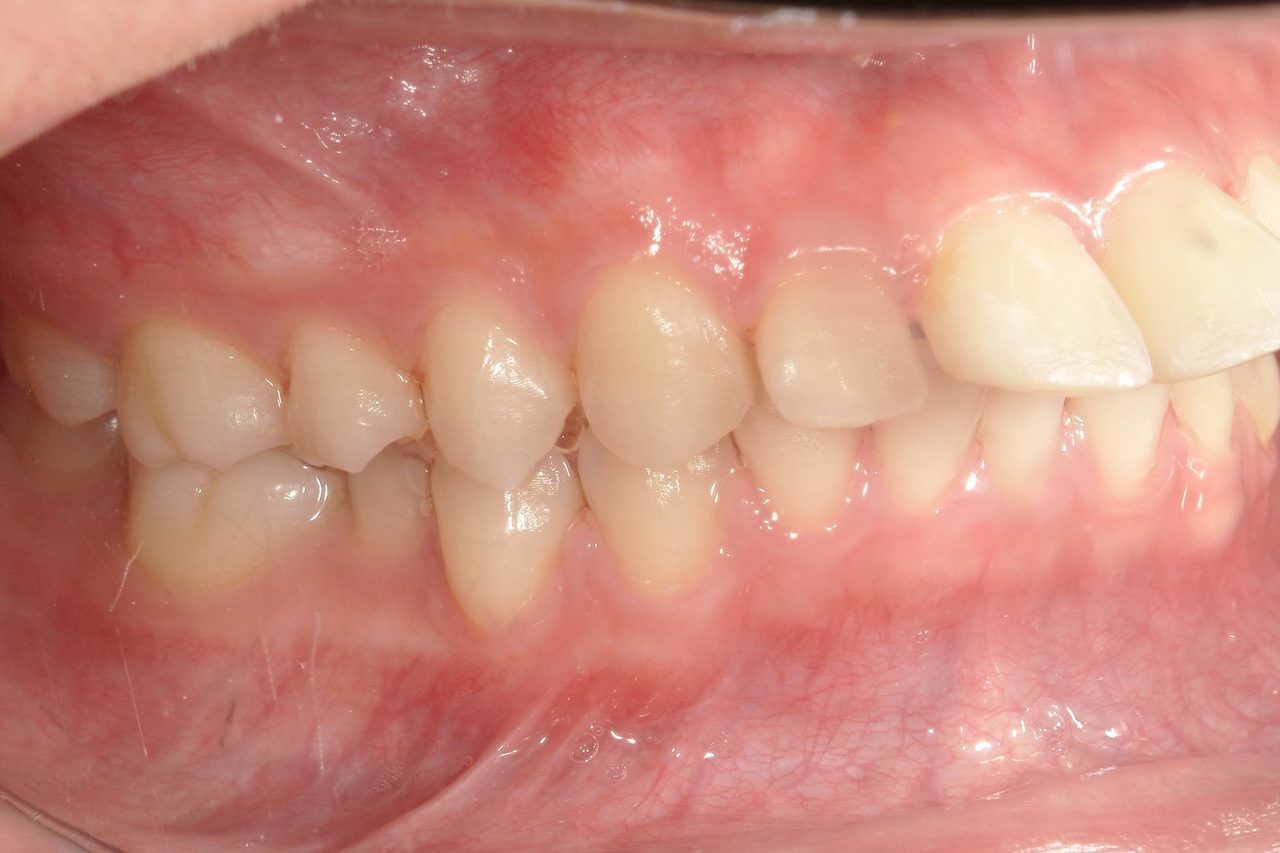

Before

浜松市中央区・自動車学校前駅のインビザラインの症例

K.M 20代女性

上の前歯が前方に出ていて横顔が気になるとの主訴でご来院。上下犬歯から犬歯までの6本が噛み合うよう、全体的に歯を内側に移動させることで、前歯の噛み合わせを整え叢生と開咬を治療しました。

​治療の期間:R5. 7/5〜R7. 1/17

​治療の価格:66万円